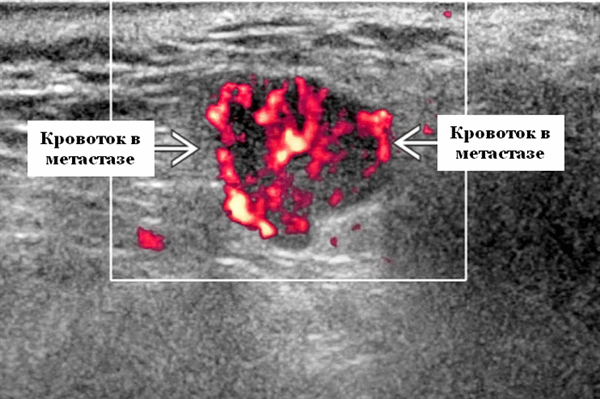

Энергетический допплер. Внутриочаговая васкуляризация. Хаотический / дезорганизованный или преимущественно периферический кровоток

- Интранодулярный кровоток хаотичный / дезорганизованный или преимущественно периферический